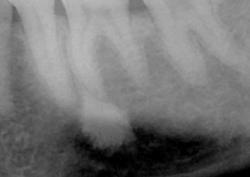

Зуб удаляют не только при сильной боли. Иногда пациент почти не предъявляет жалоб, но на рентгеновском снимке видно воспаление у корня, трещину, разрушение ниже десны или риск осложнений для соседних зубов. В таких ситуациях врач предлагает удаление как безопасный выход и заранее объясняет, какие варианты восстановления подойдут после заживления.

Метод выбирают по рентгеновскому снимку и осмотру. Врач учитывает форму корней, объем разрушения, состояние кости и мягких тканей. В практике применяются:

Без диагностики качественно удалить зуб сложно. В КДС перед вмешательством врач проводит осмотр, оценивает состояние десны, соседних зубов и прикуса. Далее выполняют рентгеновский снимок, чтобы увидеть корни, форму каналов, состояние кости и возможные воспалительные изменения.

Диагностика помогает выбрать тактику и снизить риск осложнений. Врач заранее понимает, потребуется ли разделение корней, наложение швов, дополнительная обработка лунки, а также прогнозирует сроки заживления.